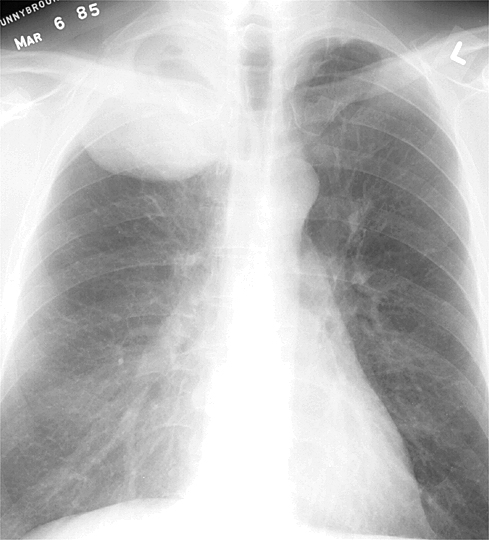

Рентгеновские снимки опухоли Панкоста